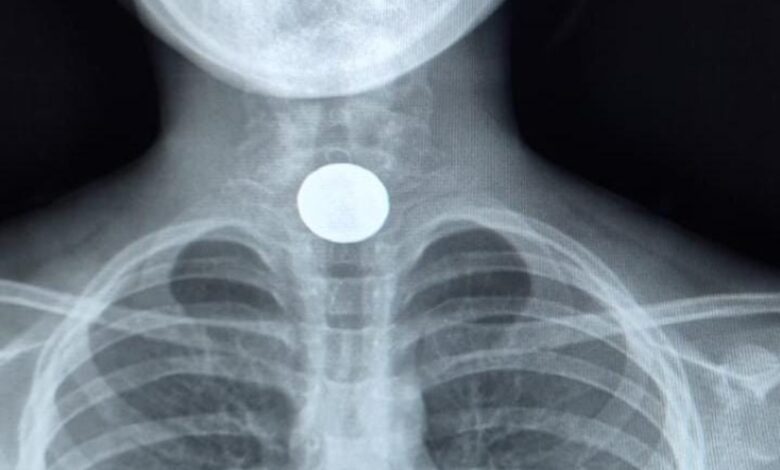

בשבוע האחרון הגיעו למלר"ד ילדים בבית החולים הציבורי אסותא אשדוד שתי ילדות, בנות 7 ו־10, לאחר שבלעו מטבעות כסף.

במקרה אחד, המטבע המשיך לקיבה; במקרה השני, נדרש ניתוח להוצאתו בשיתוף פעולה של מחלקת גסטרו-ילדים של ביה״ח.